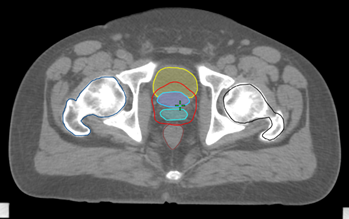

Planning Activities

Prostate Case – Contouring

Prostate Case – Planning